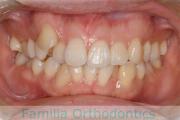

歯並びをきれいにしたいということで来院されました。上下左右から小臼歯を抜歯して、マルチブラケット法を行っています。2年弱、25回程度の通院が必要でした。

かなり強い叢生(でこぼこ、凹凸、ガタガタ)ですので、保定をしっかりしないと後戻りのリスクがあります。